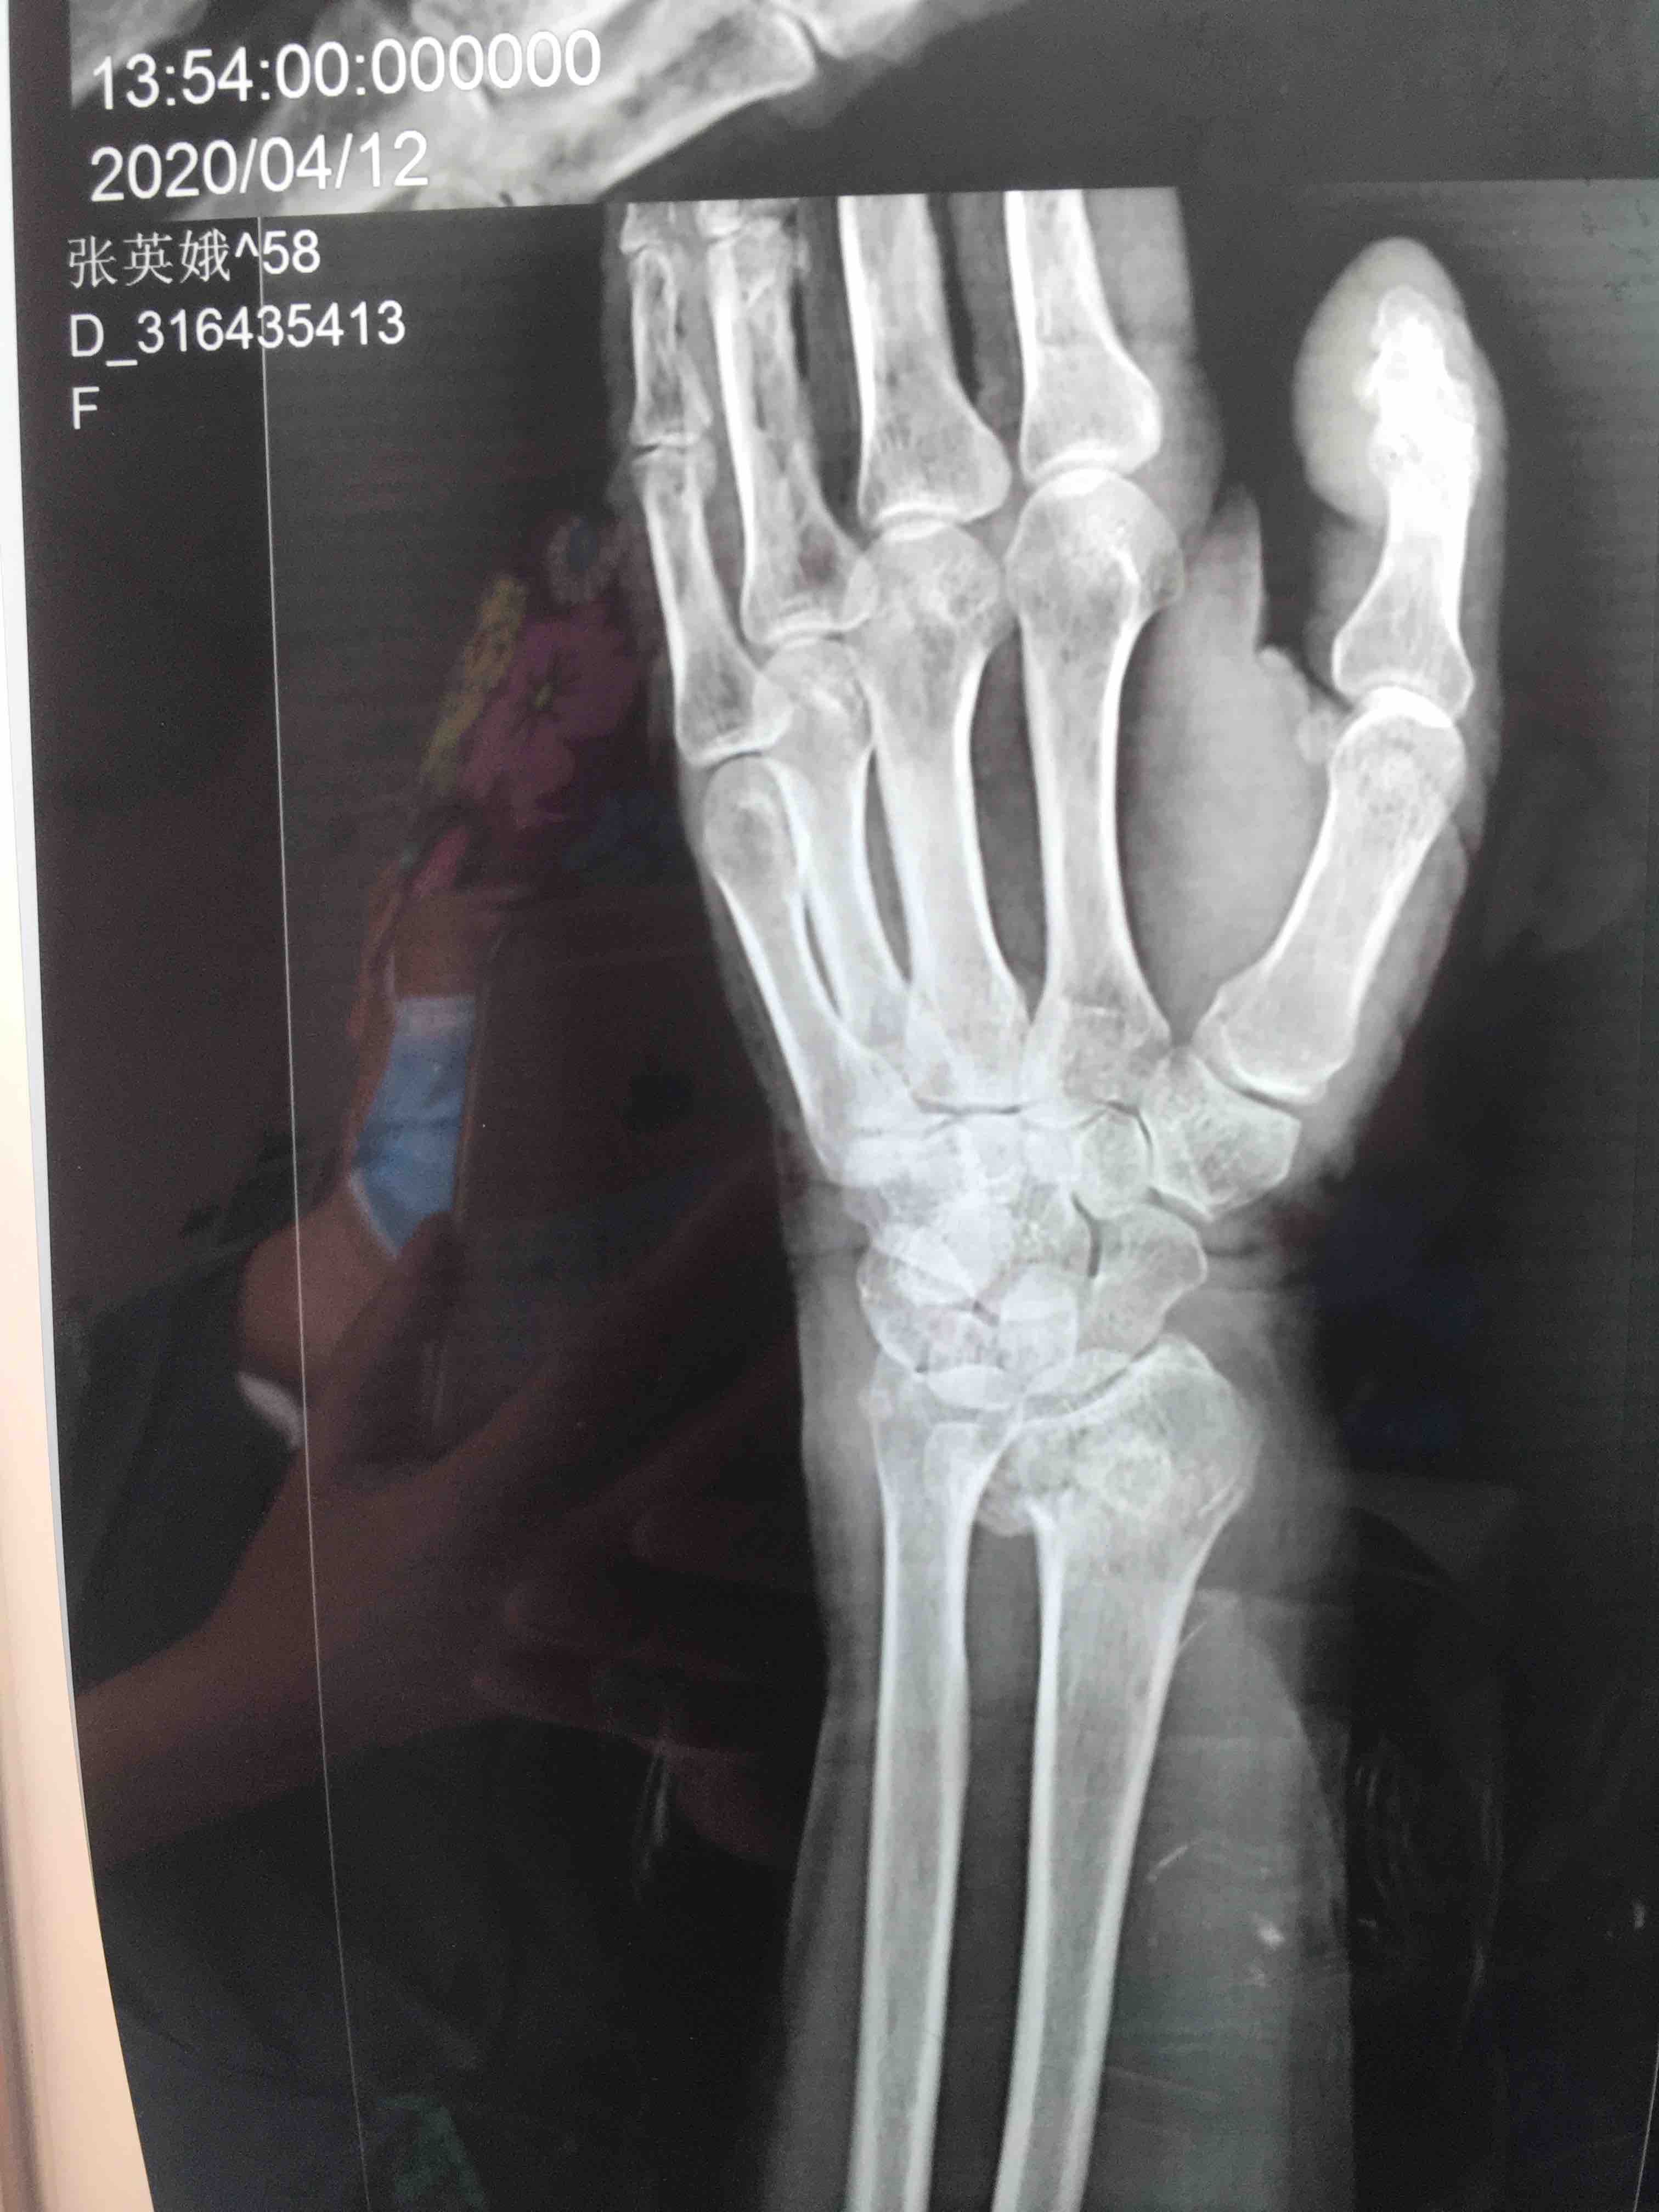

生命体征平稳,心肺复未见异常。左腕部肿胀明显,局部皮色皮温正常,畸形,压痛及纵向叩击痛阳性,腕关节活动受限,感觉血运正常。

诊断左colles骨折

在臂丛下行切复内固定术,术后抗炎消肿等处理。